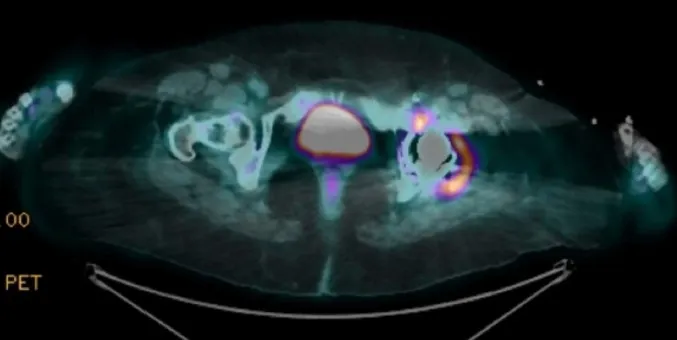

O **PET-CT** (imagem abaixo) revela hipercaptação no quadril operado, adenopatia ilíaca e foco nodular em reto abdominal: inflamação “acendendo” onde houve vazamento de cimento. O filme mental começa a focar: **reação sarcoide-like induzida por adjuvante?**

* **Imagem com mapa da inflamação**: PET-CT positivo no sítio da prótese e cadeias linfáticas adjacentes.

* ECA elevada e PET “quente” próximo à prótese apoiam granulomatose.